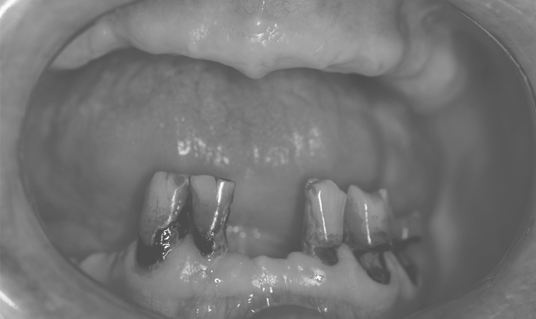

Когда применяется концепция All-on-4?

Мало зубов

Пародонтоз зубов

Отсутствие зубов

Наши работы